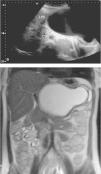

a) Ecografía abdominal que reveló masa quística de 10 x 15cm en epigastrio, anterior al estómago (EST) y bazo (BZ), sin contacto renal ni a retroperitoneo, de paredes gruesas, sin señal doppler en su interior, y sin definir su procedencia. b) RNM que reveló una lesión bien delimitada de 18 x 10 x 11,8cm en curvatura menor gástrica, con pared fina excepto en su borde lateral izquierdo donde existía doble contorno y lobulación.

Ante el tamaño de la lesión y el episodio agudo, se decidió intervención quirúrgica diferida a la semana 16.ª de gestación. Previamente a la cirugía, se efectuó RNM que reveló una lesión bien delimitada de 18 x 10 x 11,8cm en curvatura menor gástrica, que rechazaba cuerpo y antro gástrico hacia atrás y a la izquierda, limitaba con el páncreas, era hipointensa en T1 e hiperintensa en T2 (fig. 1b). Los hallazgos sugerían un quiste de duplicación gástrica.

Mujer de 21 años, de nacionalidad rumana, que vivía en España desde hacía 2 años y que no había viajado recientemente, embarazada de 13 semanas, que acudió a Urgencias por dolor en epigastrio de inicio súbito. Se palpaba masa dolorosa de gran tamaño en epigastrio. Analítica normal en sangre, excepto Hb 10,1g/dL y 15.600 leucocitos (85% neutrófilos). Ecografía ginecológica normal. Ecografía abdominal que reveló masa quística de 10 x 15cm en epigastrio (fig. 1a). La paciente permaneció ingresada y mejoró con tratamiento sintomático.